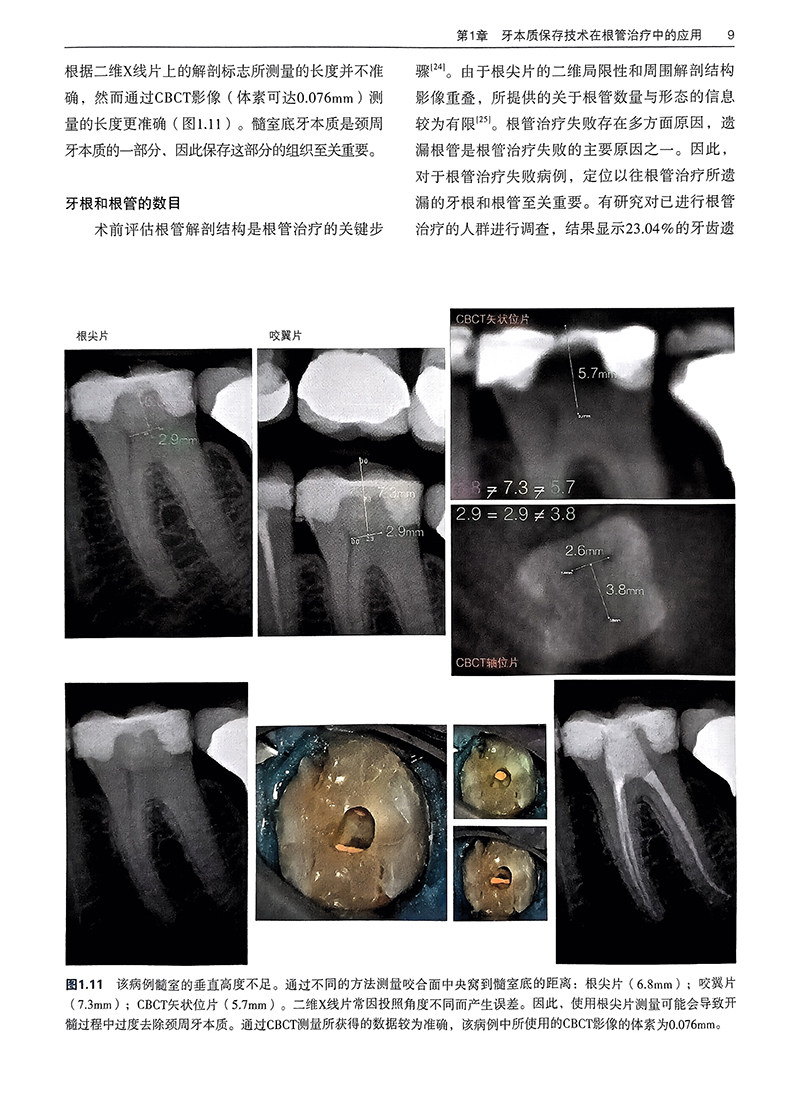

第1章 牙本质保存技术在根管治疗中的应用